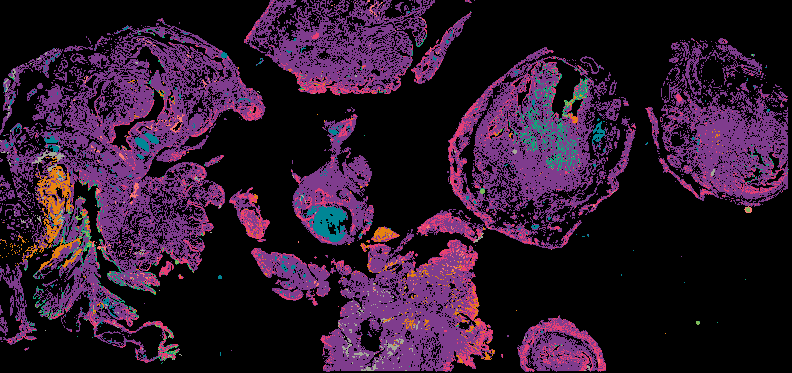

Micronuclei Rupture in High-Grade Serous Ovarian Carcinoma (HGSOC)

From 'Multimodal Spatial Profiling Reveals Immune Suppression and Microenvironment Remodeling in Fallopian Tube Precursors to High-Grade Serous Ovarian Carcinoma'.